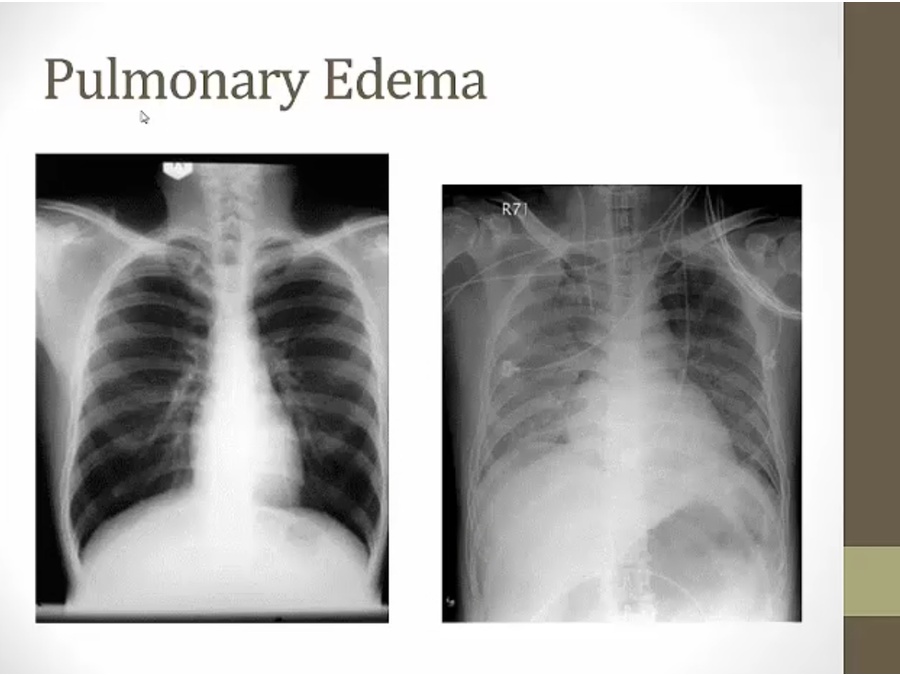

21 Xray

left normal: lung fields black

right: puffy white stuff, enlarged heart

fluid filling space between alveoli and bronchi

blunting of costophrenic angle